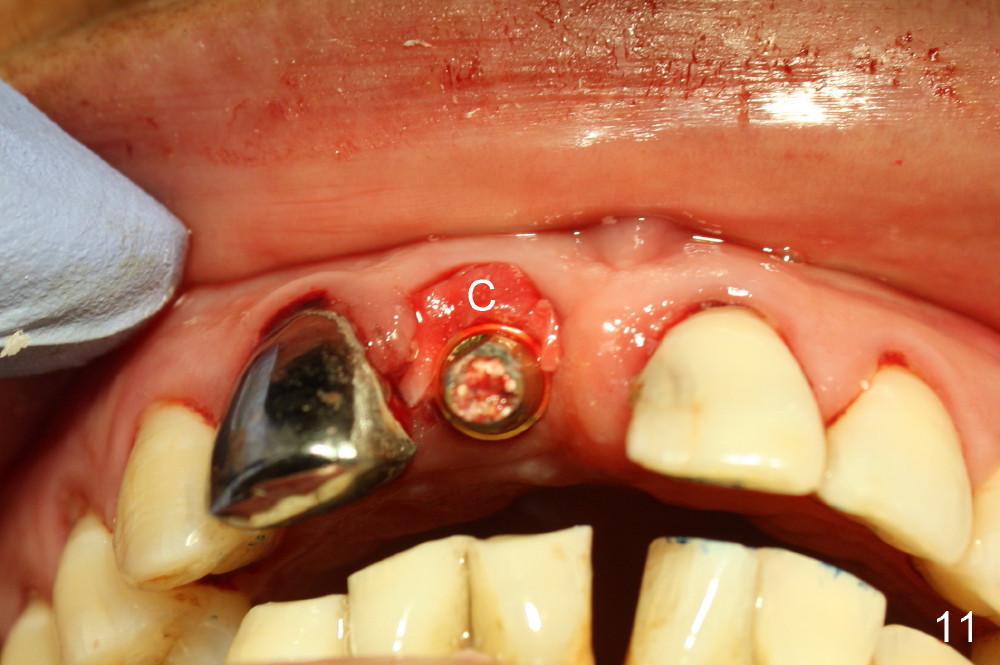

A 64-year-old lady requests replacing #7 and 8 crowns (Fig.1,2). When #8 is extracted, the labial plate is found to be missing (Fig.3). Following 2 mm pilot drill (Fig.4,5 P), 3.8 mm tap drill (Fig.6,7 T) and 4.5x14 mm implant (Fig.8 I) and 4.8 mm abutment (Fig.9 A), corticocancellous bone is harvested from the left tuberosity and placed in the labial gap of the socket (Fig.10 G). Collagen dressing is placed over the bone graft (Fig.11 C). The former is secured in place by an immediate provisional (P).